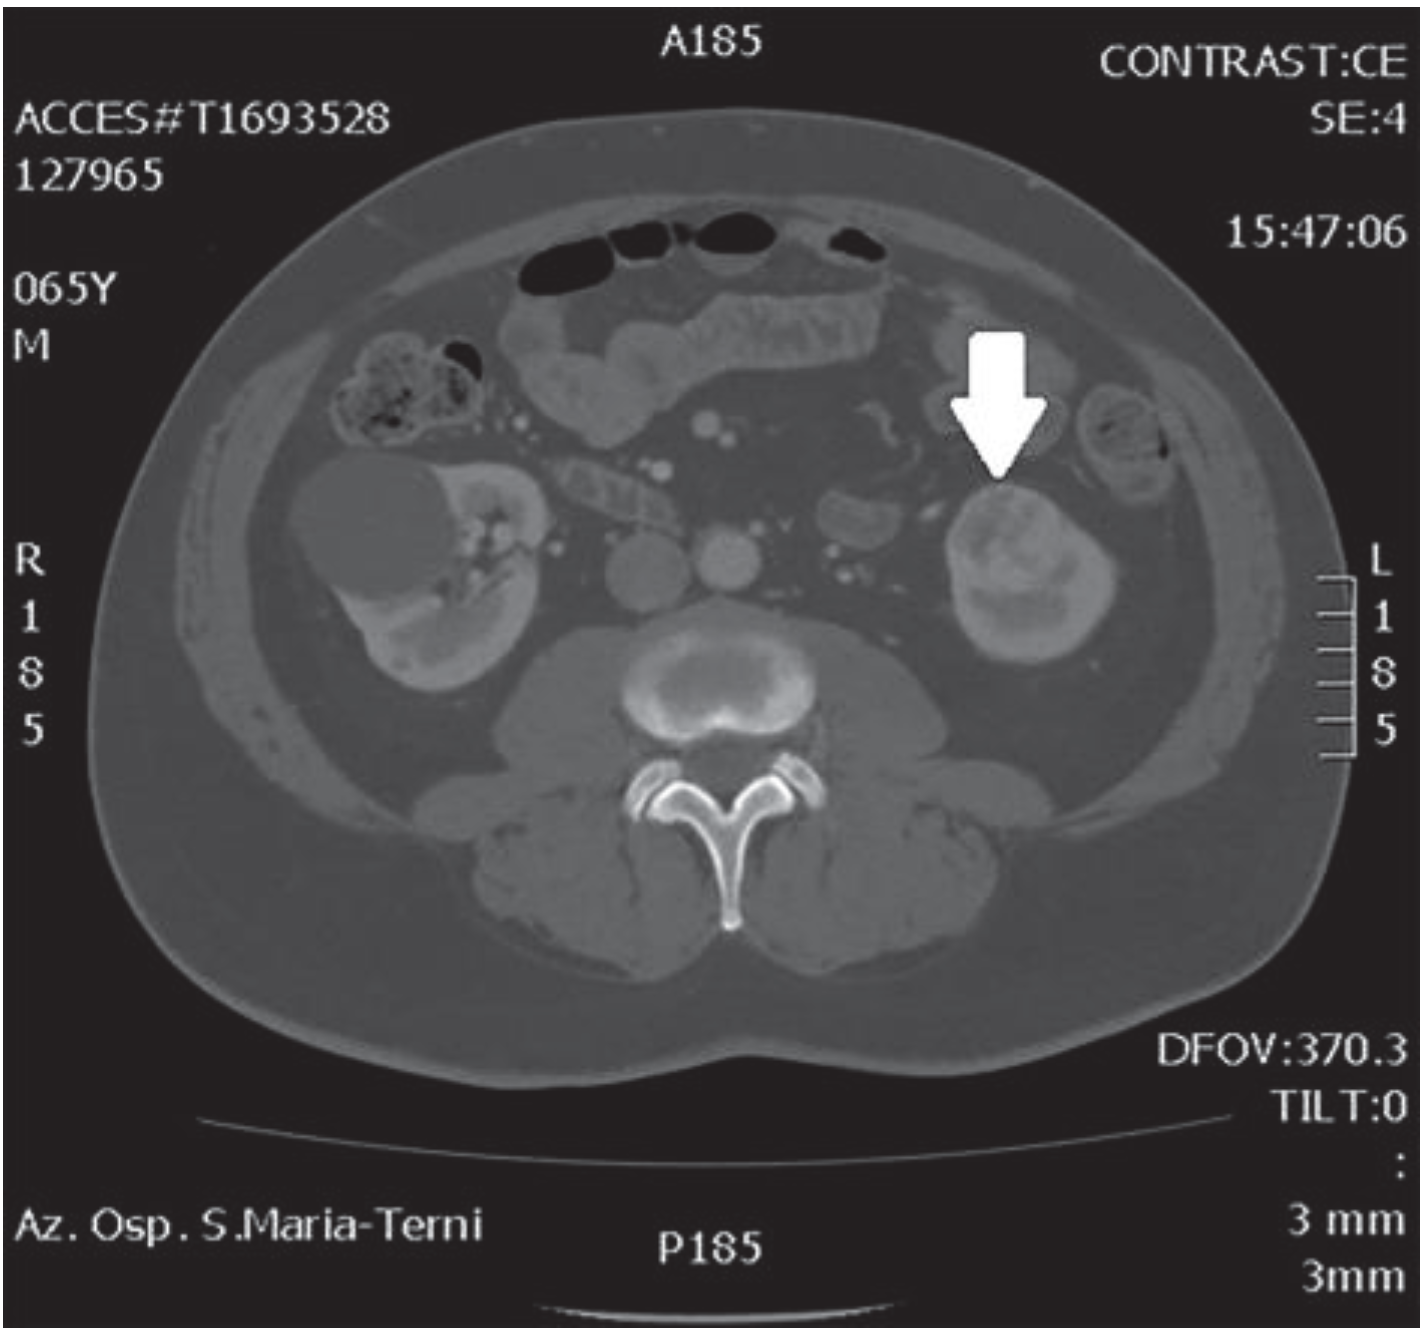

In October 2018, a 66-year-old man with hypertension and no significant prior surgical history showed a serum PSA level of 4.5 ng/mL. At clinical stage T1c, Gleason score 6 (3 + 3) PCa was diagnosed in 11 out of 22 core biopsies, all in the right side of the gland. A total body bone scan was negative for metastasis. An abdominal CT scan showed no evidence of pathologic pelvic lymphadenectomy but highlighted two incidental heterogeneous enhancing solid masses in the left kidney that were suspicious for renal cell carcinoma: one sized 32 mm in the lower pole and the second of 10 mm in the mesorenal site. A 6-cm asymptomatic simple cyst was found in contralateral kidney. Serum creatinine was 1.43 mg/dL. CT imaging of renal masses is shown in Figure 1 and Figure 2.

Figure 2.

Renal mass of the lower pole.